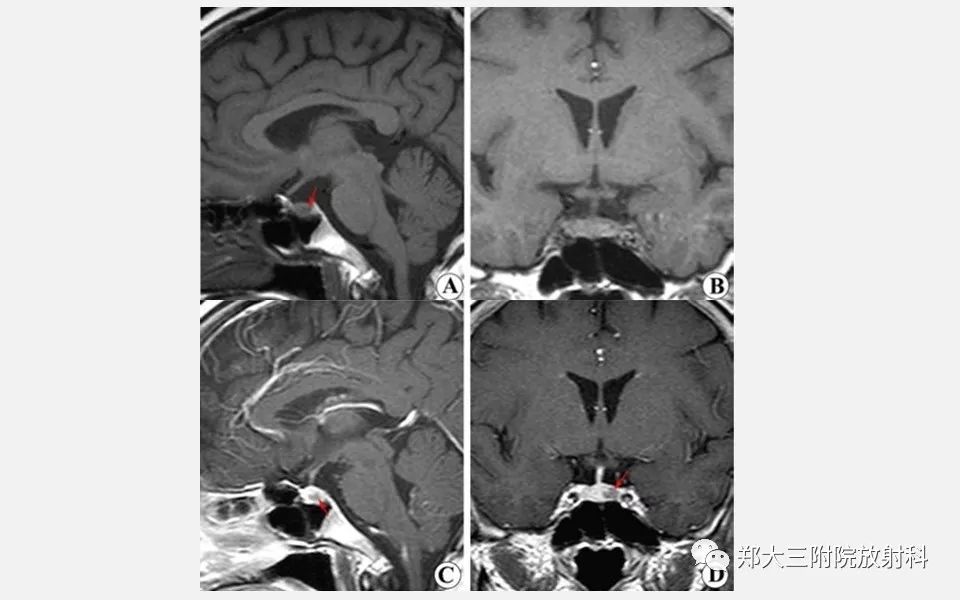

垂体增生的影像表现

【PPT】垂体增生的影像表现